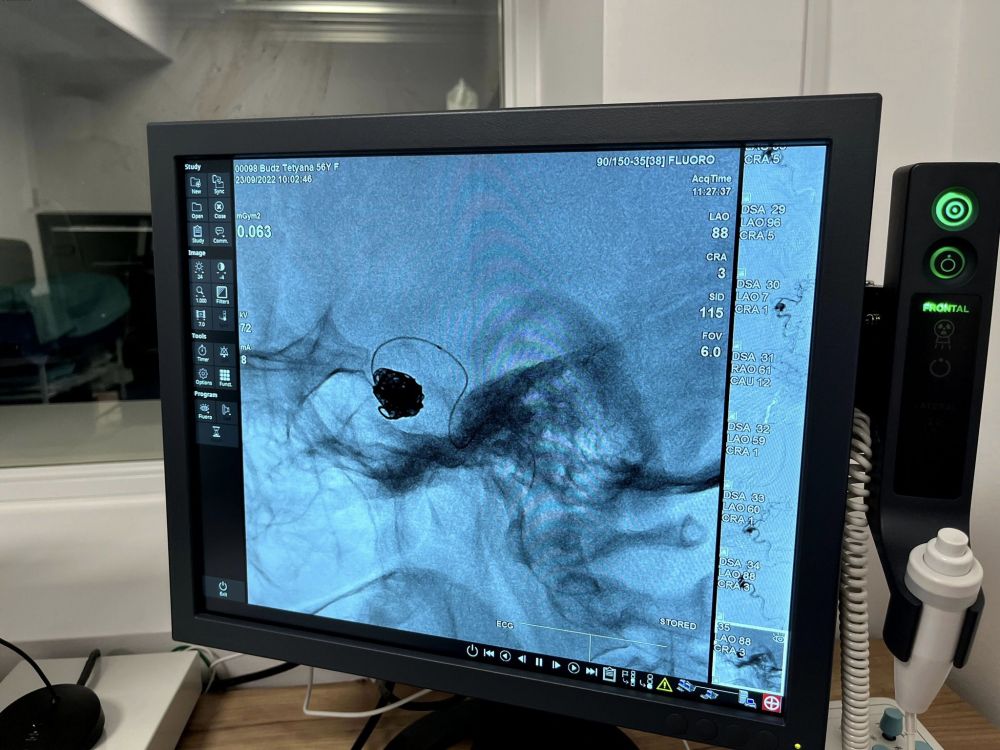

У львівській лікарні медики успішно прооперували жінку з великою аневризмою мозкової артерії, яка була розміром півтора сантиметра.

«Ми розширили географію надання новітньої нейрохірургічної та нейрорадіологічної допомоги для наших пацієнтів з різних районів міста та області. Як результат – цими днями медики врятували життя 56-річної пацієнтки з величезною аневризмою, розміром півтора сантиметра», – повідомили у Першому медичному об’єднанні Львова.

Після діагностики у жінки виявили велику аневризму мозкової артерії. І вже наступного дня спеціалісти відділення реперфузійної терапії та радіології виконали емболізацію – закриття аневризми з допомогою мозкових спіралей. Тому операція відбулась без розрізів – лише одним проколом, довжиною до 5 мм.